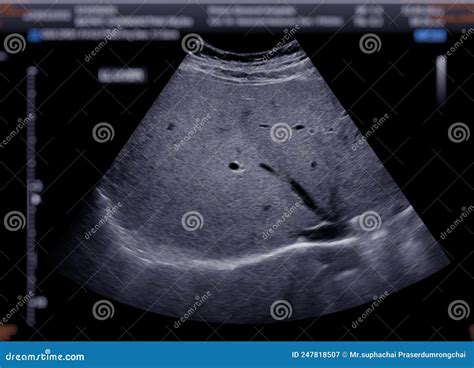

Interpreting the results of a liver ultrasound involves assessing the images for any abnormalities. A normal liver ultrasound will show:

• Size and Shape: The liver should be of normal size and shape, with smooth edges.

• Echogenicity: The liver tissue should have a uniform echogenicity, indicating a healthy structure.

• Blood Flow: Normal blood flow through the liver and its vessels.

• Absence of Abnormalities: No cysts, tumors, or other abnormalities should be present.